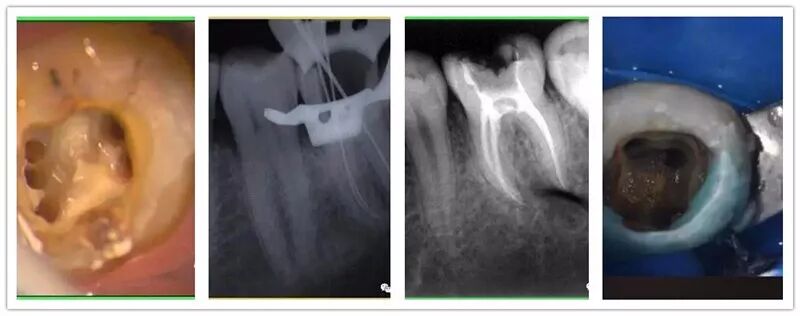

| 11:00-12:00 | 橡皮障的使用方法及注意事项;开髓方法及直线通路的建立;工作长度如何确定及方法 | 左宗波 |

| 14:00-15:00 | 根管预备方法及冲洗方法;根管充填方法及评估 | 左宗波 |

| 11:00-12:00 | 根管治疗术前检查及方案确立;浸润麻醉的实施;术区隔离及洞型恢复;髓腔清理及治疗通路的建立;封药的选择 | 陈希 |

| 14:00-15:00 | 实操演示 | 陈希 |

2012年至2013年于北京天坛口腔医院研修学习热牙胶及修复一年,擅长牙体牙髓热牙胶根管的预备和3d充填,前牙美学修复及复杂阻生牙的微创拔。

宇森医疗特聘讲师,各地开展根管内训,已赴福建、新疆、广州等地开展根管公开课。